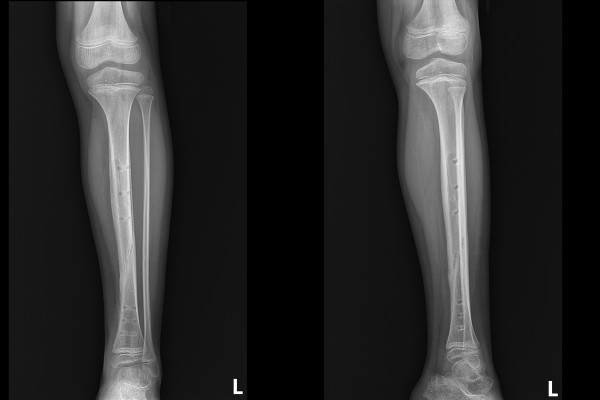

강원도 철원군에 거주중이신 8세 남자아이 환자분께서 좌측 정강이뼈 골절로 내원해주셨습니다. 약 1주일 전 시소에서 떨어지며 다치셨고, 타병원에서 통깁스를 통한 보존적 치료를 시행중이었으나, 뼈가 어긋나 수술적 치료가 필요하다는 소견을 듣고서 보호자분께서 검색을 하여 골절수술을 많이 하고, 족부전공자가 있는 저희 병원을 찾아오시게 되었다고 말씀하셨습니다.

내원 당시 X-RAY를 보면 정강이뼈가 부러져서 각변형(각도 변형)되어 정렬이 흐트러진 것이 확인됩니다.

측면에서 확인해봐도 골절로 인해 정강이뼈가 어긋나있음이 확인되어 소아 정강이뼈 골절(Fx. distal tibia shaft lowerleg Lt.)을 진단하였습니다.